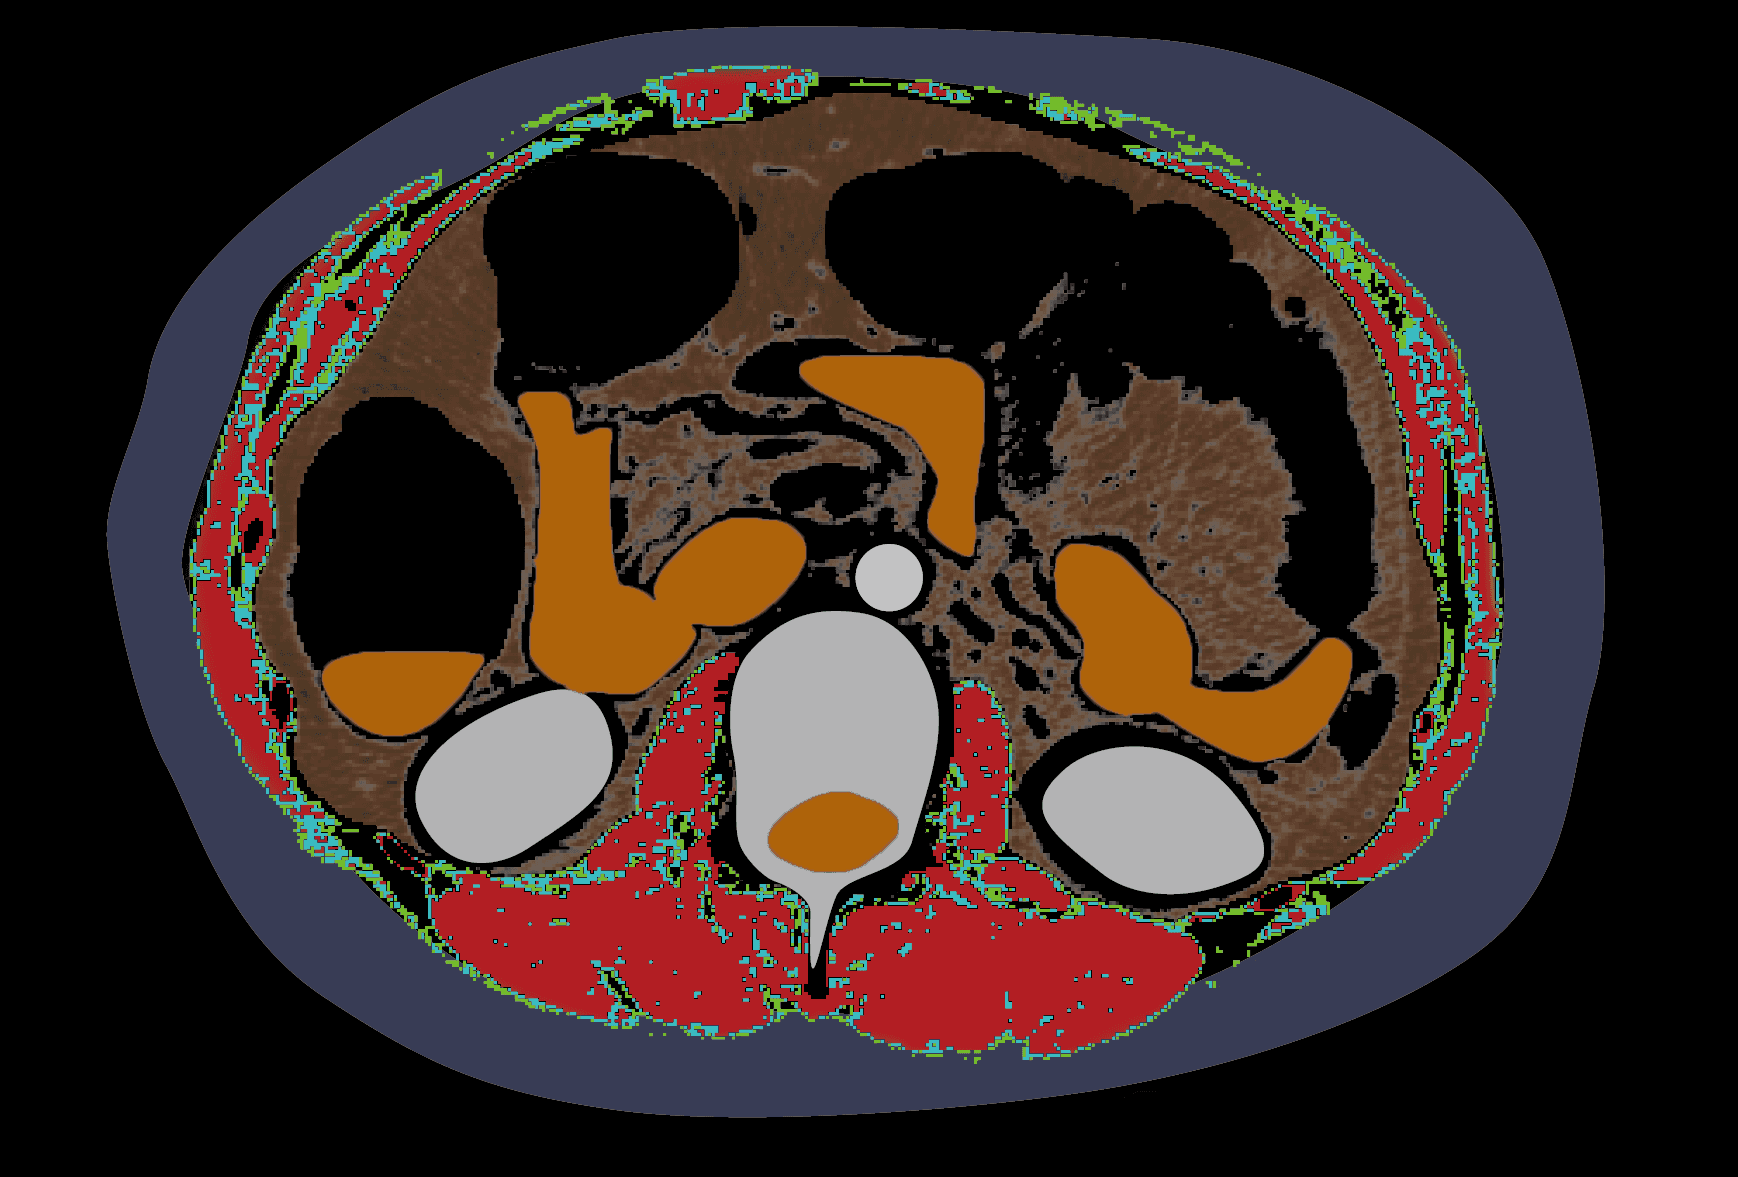

복부 CT 영상에서

L3 영상 자동 추출

근육 및 지방 정보 상세 분석

복부둘레근육 분할 성능 96%

NAMA, LAMA, IMAT가 무엇인가요? ¹